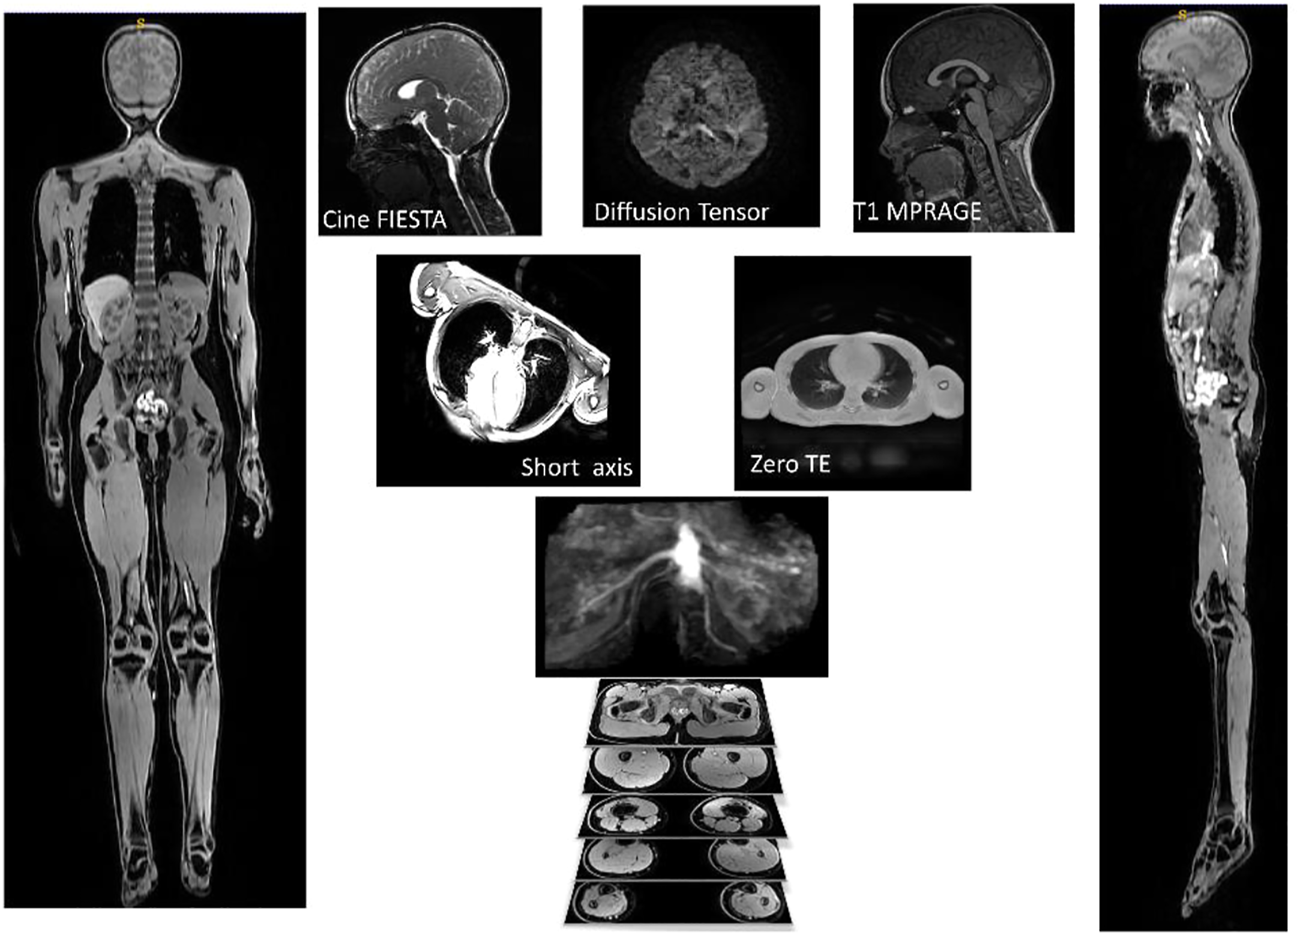

The final image protocol is shown in Table 2. From the 31 children participants recruited, one child could not tolerate the MRI scan, finding the breath holds particularly uncomfortable. Several children struggled with the breath holds during cardiac and lung imaging. Children and their parents reported positively on the ability to watch video during scan, having break during protocol with juice and snack and showing children samples of images acquired during the scans. Sample images from the sequences are shown in Figure 2.

FIGURE 2

Example of images used for one participant. AutoBind whole body images on the right and left was used for bones and muscle, top three pictures (Cine FIESTA, DTI and T1 MPRAGE) were used to model the brain, under the brain are two pictures of the sequences (Short Axis and Zero TE) used for the heart and lungs.